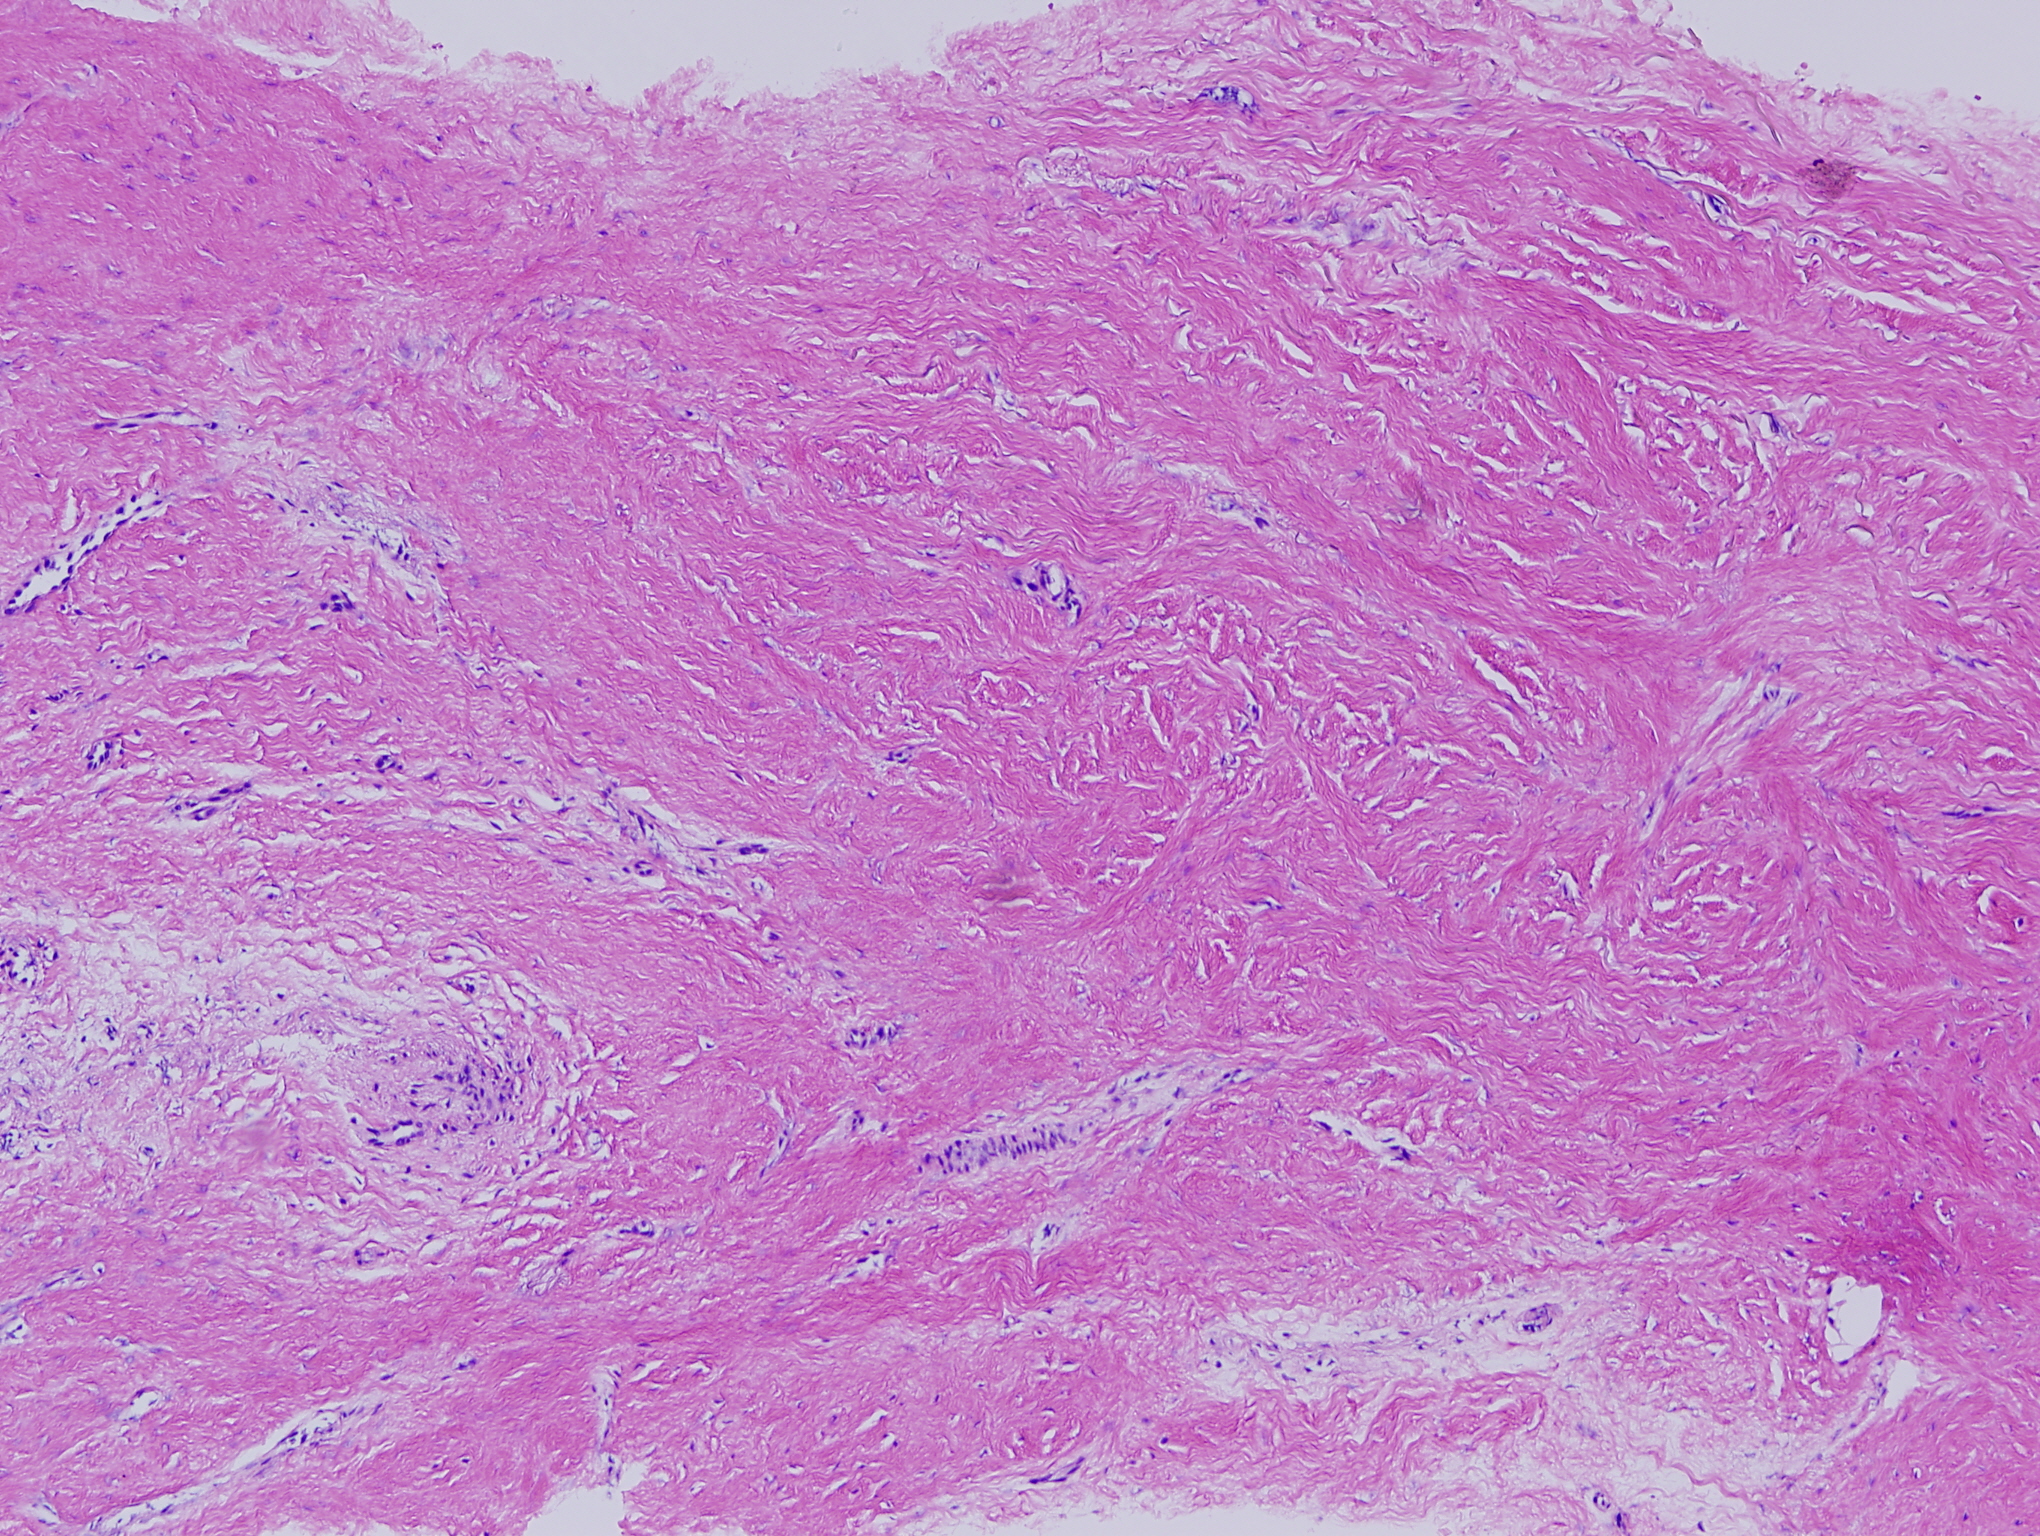

This photomicrograph depicts Alloderm that was placed 6 months prior to this biopsy (a small section removed while adding more).  Note how robust and "alive" the tissue appears: ingrowth of vessels, fibroblasts, collagen.